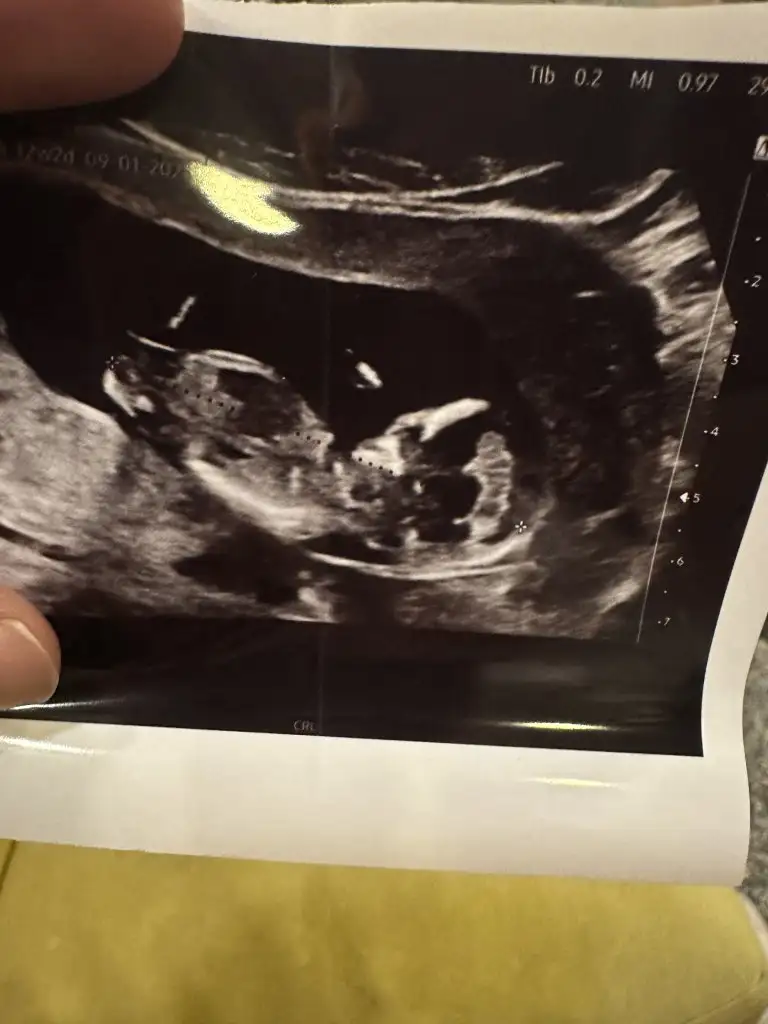

Erkek demiştim dimi kız sana hatırlamıyorum koç gibi yatıyo işteCanım sana yeni resimle geldim![]()

Benimkinde bi tahminde bulunurmusunjz 9+5 karından ultrasonSizin beybi de küçük:)

ErkekBenimkinde bi tahminde bulunurmusunjz 9+5 karından ultrason